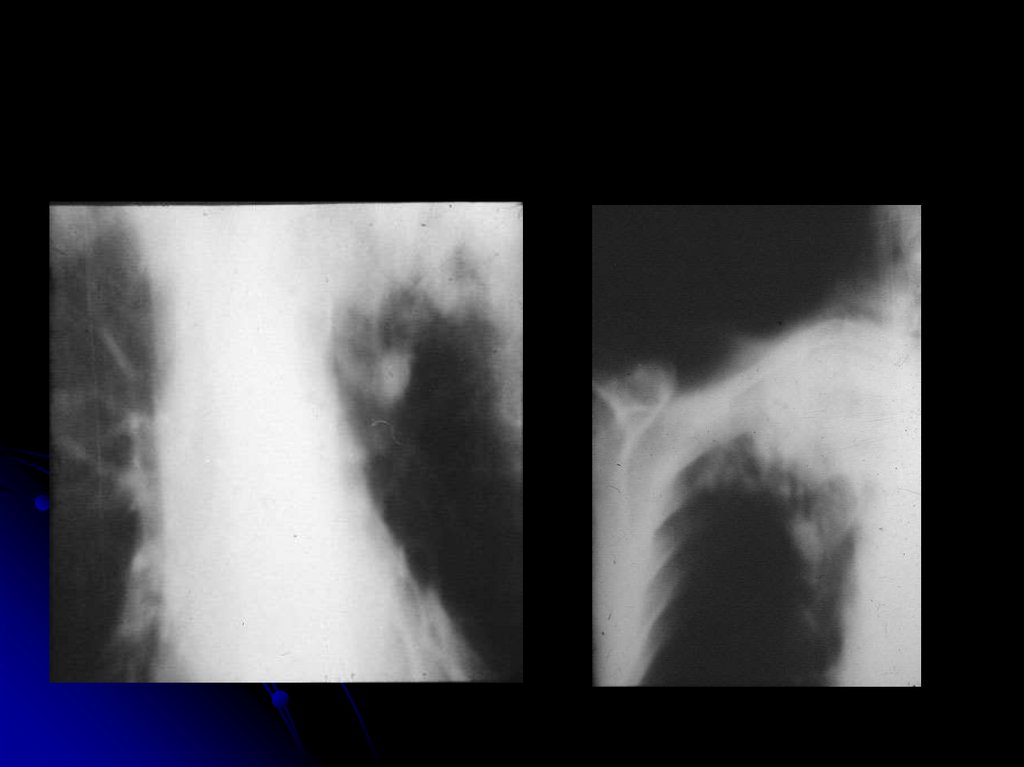

Абсцесс в результате обтурации крупного бронха

14. Абсцесс в результате обтурации крупного бронха

15. Абсцесс в результате обтурации крупного бронха

16. Абсцесс в результате обтурации крупного бронха